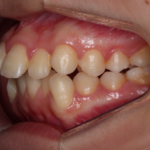

【空隙歯列、叢生】インビザライン症例:隙間とガタガタが気になる

治療前 治療後 症例の詳細 主訴 隙間とガタガタが気 ...